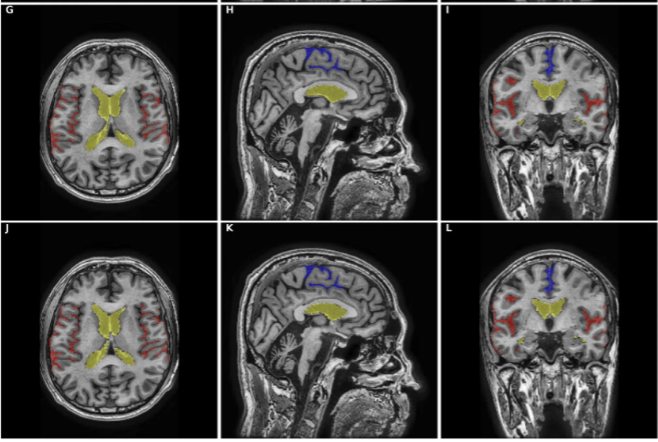

AI 모델이 MRI 영상에서 해마, 측뇌실, 지주막하 공간 등 주요 뇌 영역을 자동으로 분할하고 부피를 측정합니다.

• Evan's Index 자동 산출: iNPH 진단의 핵심 지표 자동 측정

• Callosal Angle 분석: 뇌량각 정밀 측정 지원

• DESH 징후 판별: 불균형적 지주막하 공간 확장 여부 분석

• 주요 해부학적 구조 3D 시각화